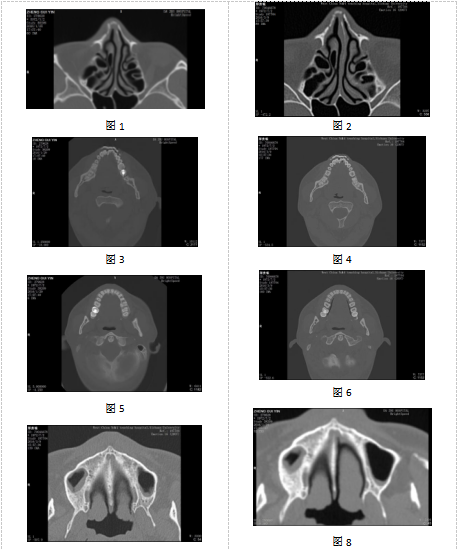

1月29日图像与3月9日图像比较,存在以下共同特征:①咬合时上下牙列形态及相对形态一致,其中右侧中切牙向内侧错位(见图3、4);②右下第二磨牙病变一致(见图5、6);③双侧上颌窦形态及慢性炎症改变一致(见图7、8);④右侧鼻骨骨皮质不连部位一致(见图9、10);⑤筛窦上部间隔分布位置及形态一致(见图11、12、13);⑥额窦左右共五个完整间隔,间隔附着位置及分隔的窦腔形态一致(见图14、15、16);⑦额窦右侧额骨气化形态一致(见图17、18);⑧额窦层面右侧顶骨形态一致(见图19、20);⑨蝶窦中间隔完整,右侧腔小于左侧腔,左右腔内另有不完整间隔均位于左侧壁,间隔位置及形态一致(见图21、22)。